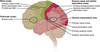

Key gyri on the lateral surface of the frontal lobe

Superior frontal gyrus

Middle frontal gyrus

Inferior frontal gyrus (pars triangularis, pars orbitalis, pars opercularis)

Precentral gyrus

Key sulci on lateral surface of frontal lobe

Superior frontal sulcus

Inferior frontal sulcus

Pre-central sulcus